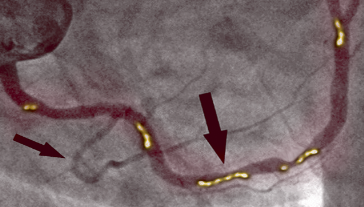

PO KÚRE

Na fotografii vpravo vidíme vyčistenú pravú koronárnu tepnu bez stôp kalcifikovaného aterosklerotického plátu u toho istého pacienta po 1 mesiaci kúry. Neexistujú žiadne smrteľné usadeniny cholesterolu. Krv voľne prúdi a okysličuje všetky orgány.